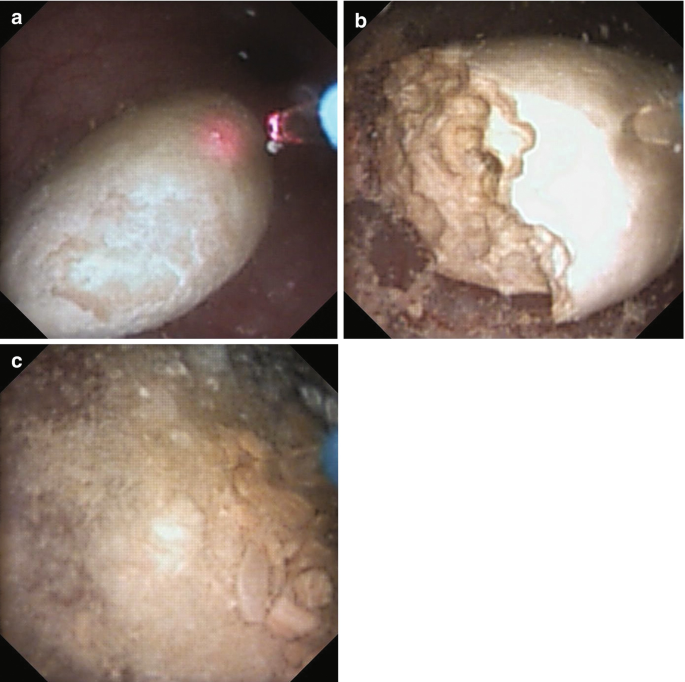

软镜已被用于治疗肾盂旁囊肿、肾盏憩室和输尿管 / PUJ 狭窄。一旦 F-URS 进入肾盂,囊肿就被识别出来,并用激光切开和引流肾囊肿壁。将切开后的输尿管支架置入囊肿并在 4 周后取出。对于憩室,在超声或透视引导下注射亚甲基蓝以识别憩室颈。集合系统用生理盐水冲洗后,内窥镜下可以看到憩室漏出的染料,然后用激光切开憩室颈部。对于输尿管狭窄,需要定位并进行全层切口。为避免血管损伤,近端狭窄在后外侧进行,远端狭窄在前内侧进行。

治疗肾盂旁囊肿、肾盏憩室和输尿管狭窄